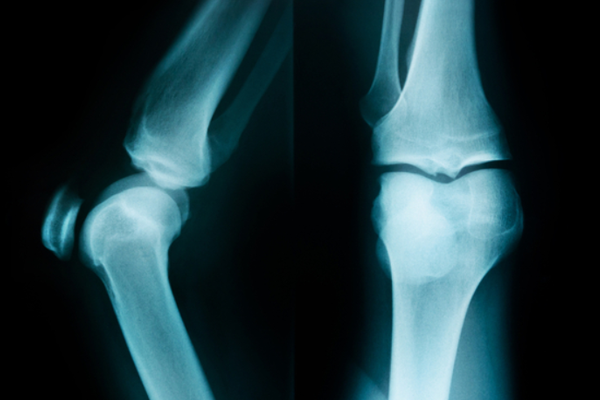

반월상연골이란 허벅지뼈(대퇴골)와 종아리뼈(경골) 사이에 위치하며, 충격을 흡수의 완충역할을 해주는 반달모양의 연골(물렁뼈)로 무릎의 안쪽과 바깥쪽에 각각 1개씩 위치해습니다. 반월상연골은 생긴 모양이 초생달과 비슷하여 반월상연골이라는 명칭이 붙었습니다. 반월상연골 파열의 원인으로는 비접촉성 손상의 갑작스런 동작 (방향 전환 및 급정지), 미끄러짐 등이 있고, 축구 및 농구 등의 과격한 운동으로 인한 스포츠 손상이 있으며 40대 중반이후로 퇴행되는 연골판, 반월상연골판이 쉽게 찢어지면서 발생하는 퇴행성 변화가 있습니다. 무릎을 많이 구부리는 일을 하는 주부들에서 가장 많이 발생합니다.